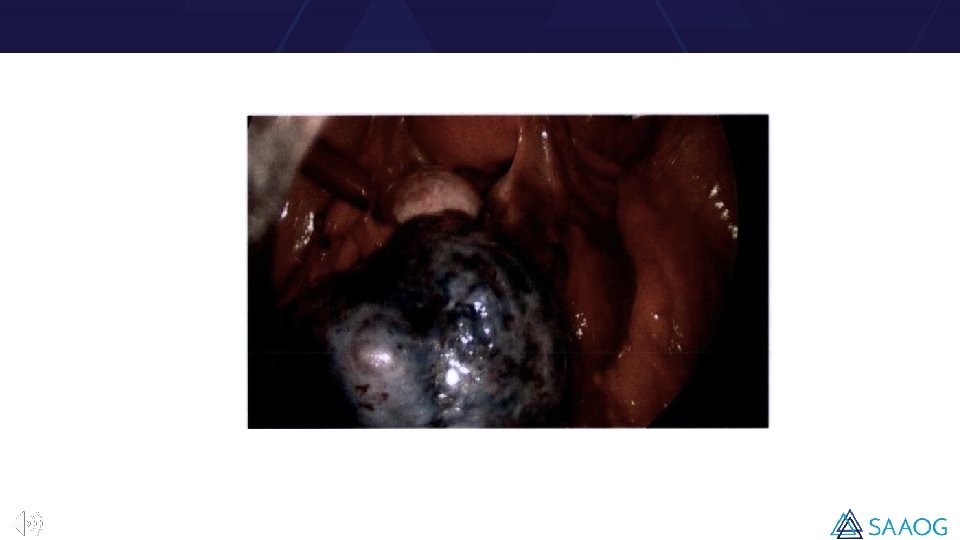

Introduction • Ovarian torsion is considered a surgical emergency. An estimated 2. 5 -7. 4% of all acute abdomen cases represent ovarian torsion. • Once the ovary is twisted, blood flow is blocked resulting in hemorrhage and congestion with further necrosis. The main parameter guiding surgeons’ decision to choose ovary sparing or removal of the adnexa is intraoperative assessment of the ovary. • Surgeons typically associate dark appearing ovaries with necrosis, and this is a common indication for oophorectomy. However, evidence suggests that despite a black appearance during surgery, ovaries recover function over time. • There are no reliable laboratory methods or imaging to predict ovarian necrosis in patients with ovarian torsion.

• Intraoperative visual assessment of the ovary (necrotic and not necrotic) was correlated with the histopathological finding (normal tissue, hemorrhage or congestion, or no necrosis). • Any tissue that had a black appearance by visual assessment or was degraded, was judged as necrotic. • Time from onset of pain to surgery, color flow in ultrasound, and ovarian size in ultrasound were further analyzed. • Cross-tabulation and chi-square test of independence were used to examine if there was a significant relationship between variables. Correlation analysis was also employed. P-values ≤ 0. 05 were considered to be statistically significant.